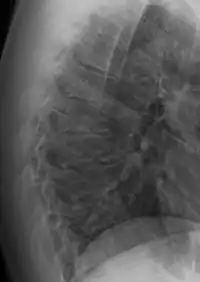

Scheuermann's disease on lateral Xray of the T spine | |

Scheuermann's disease is a self-limiting skeletal disorder of childhood. Scheuermann's disease describes a condition where the vertebrae grow unevenly with respect to the sagittal plane; that is, the posterior angle is often greater than the anterior. This uneven growth results in the signature "wedging" shape of the vertebrae, causing kyphosis. It is named after Danish surgeon Holger Scheuermann.[3][4][5]

The seventh and tenth thoracic vertebrae are most commonly affected. It causes backache and spinal curvature. In very serious cases it may cause internal problems and spinal cord damage, but these cases are extremely rare. The curvature of the back decreases height, thus putting pressure on internal organs, wearing them out more quickly than the natural aging process; surgical procedures are almost always recommended in this case.

Diagnosis is typically by medical imaging. The degree of kyphosis can be measured by Cobb's angle and sagittal balance.